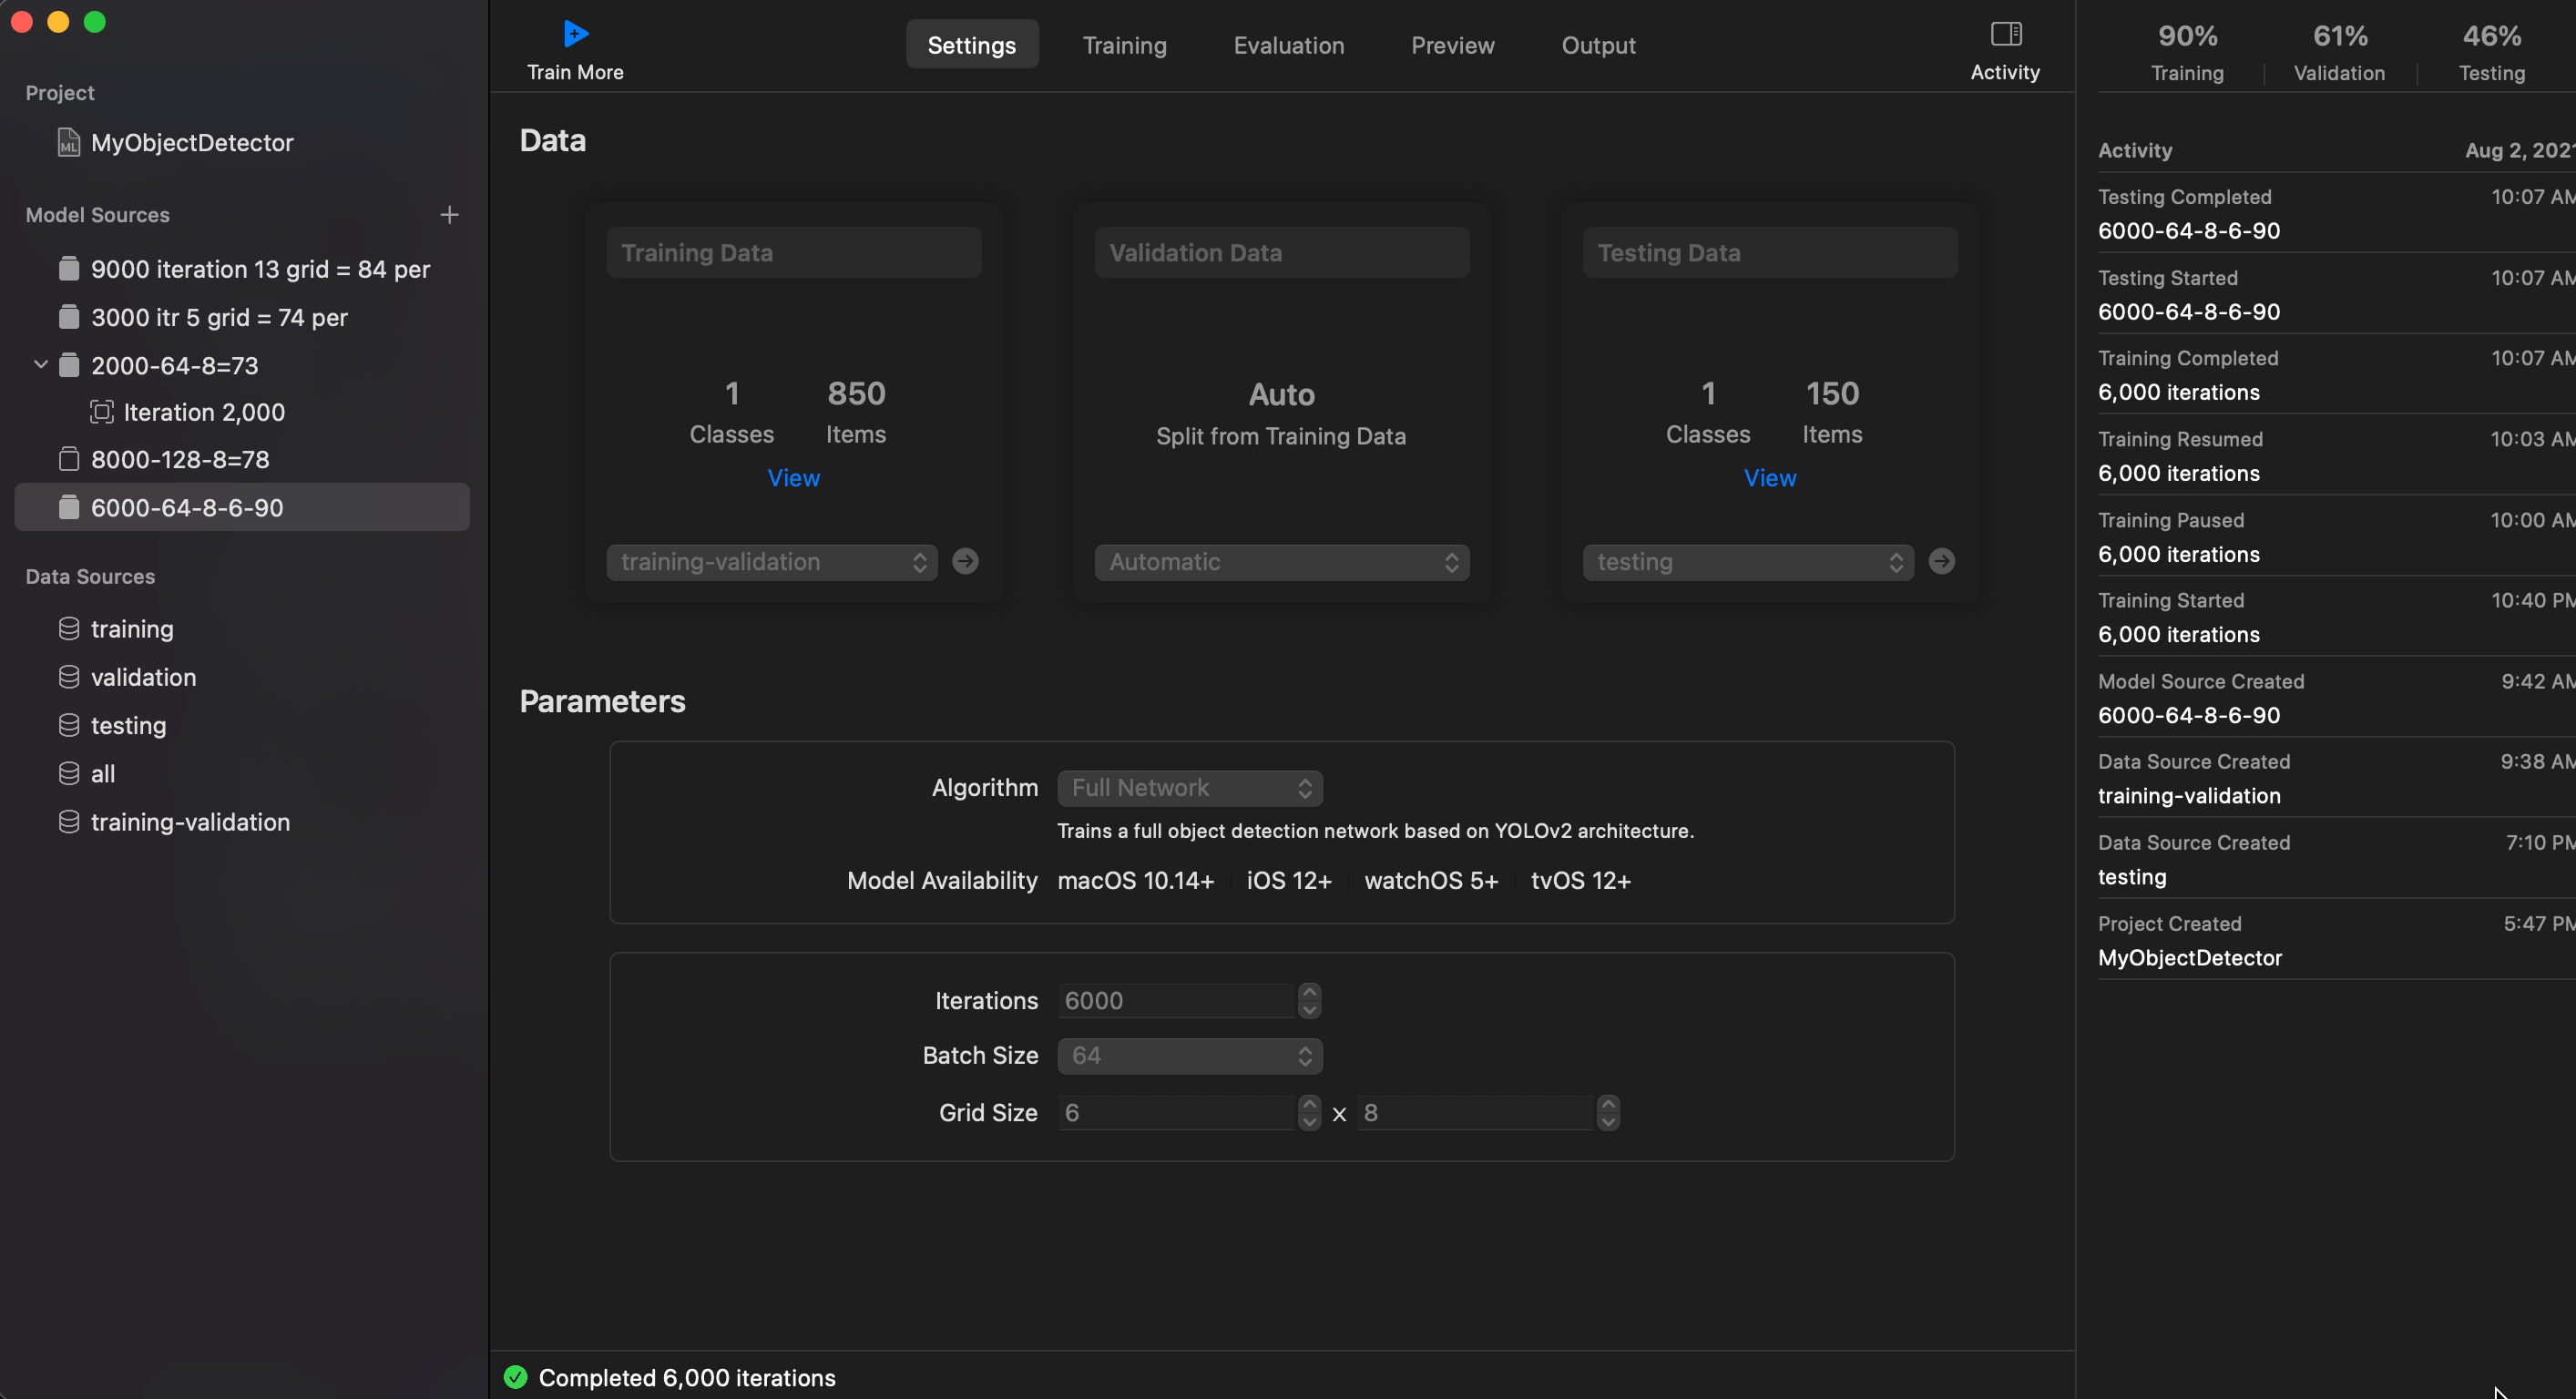

- Iteration: 6000

- Grid Size: 8 x 6 or could be 8 x 8

- Training and Valiation set: 850

- Testing set: 150

- Batch Size: 64

Loss: 1.013

I/U 50%: 90%

Training: 90%

Training: 71%

Training: 46%